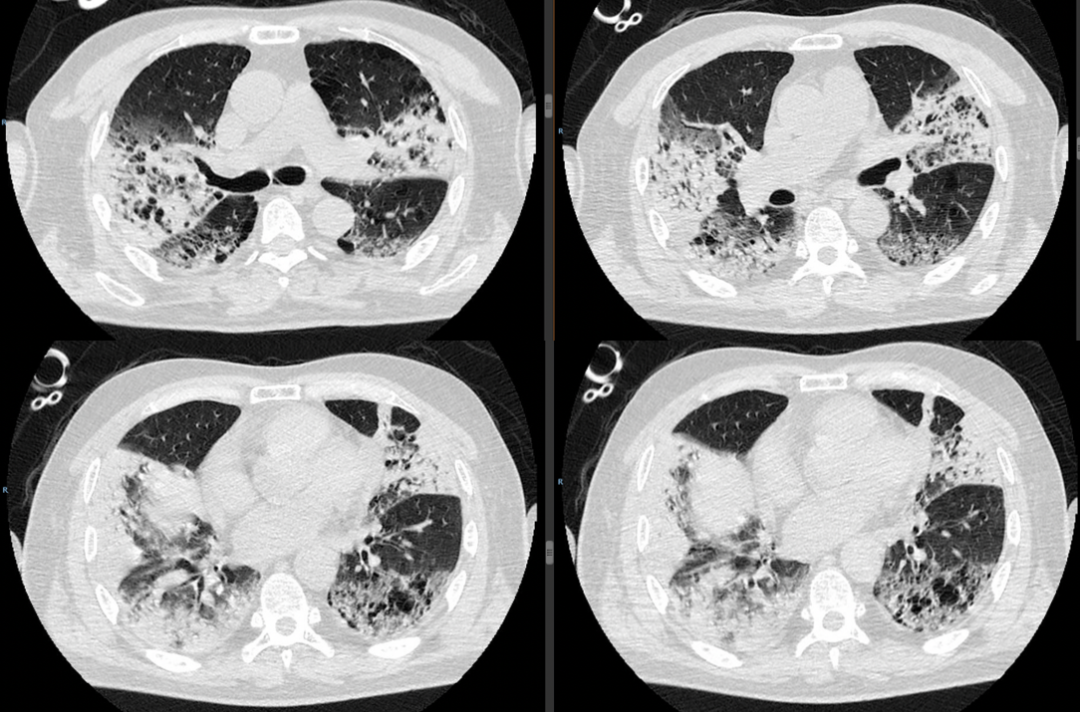

右肺中下肺野、左肺上叶有渗出性病灶,局部呈铺路石征、支气管充气征阳性,病灶分布无规律,包括磨玻璃影、实变、气腔实变、肺体积缩小,以感染性病变后纤维化改变为主(图1)

图1  患者复查HRCT